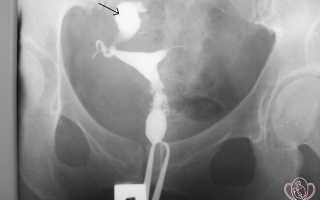

Гистеросальпингография (ГСГ) — это рентгенологическое исследование матки и труб, которое позволяет получить объективную информацию об их состоянии, позволяет оценить проходимость и функциональное состояние маточных труб, рельеф и размер слизистой оболочки матки.

| Контроль проходимости маточных труб под рентгенологическим контролем. Определяется правый сактосальпинкс. Сактосальпинкс обозначен стрелкой. Зубцы пулевого зажима видны внизу изображения | ![]() |